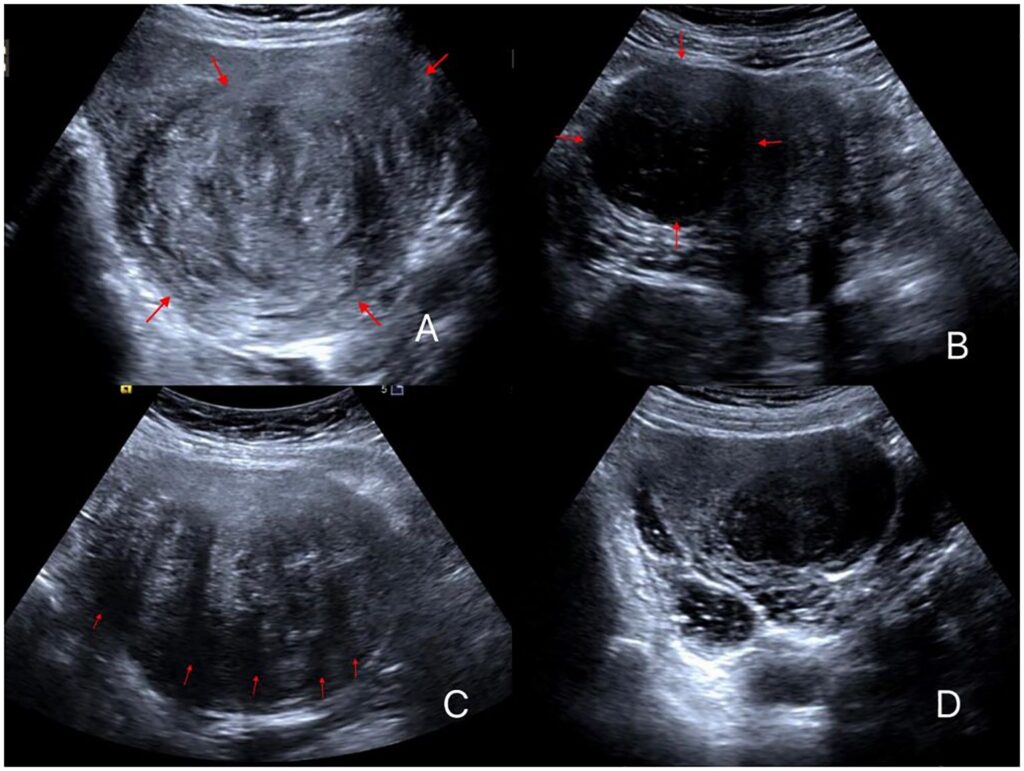

Doctors typically diagnose fibroids using:

Pelvic examination

Ultrasound scan

MRI scan (for detailed assessment)